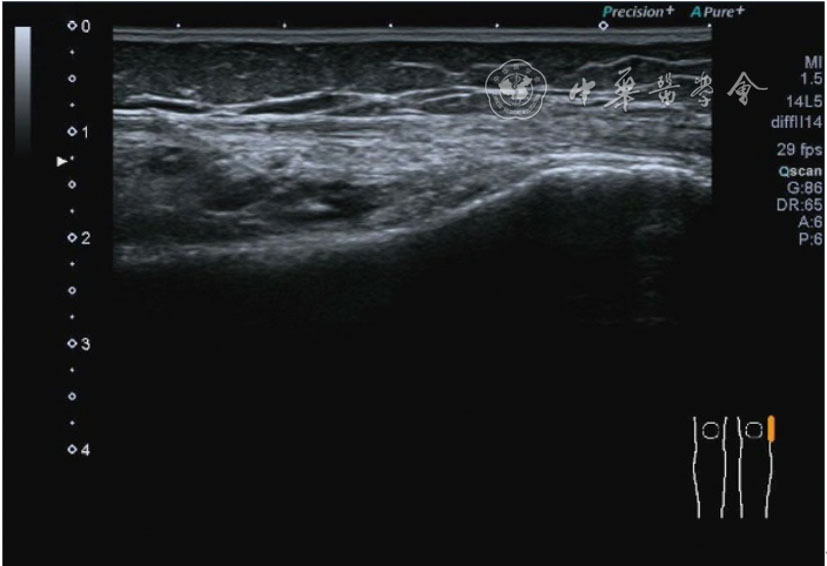

1.关节内表现。(1)骨改变。表现为骨末端或关节周缘出现的骨质局部突起改变,其后方伴或不伴有声影,多见于膝关节内侧缘和外侧缘(图1)。(2)软骨改变。股骨关节面改变可以在长轴及短轴切面显示,嘱患者屈曲膝关节,足平置于检查床,股骨滑车及股骨髁上半部分的关节面即可轻松显示。超声探查可见股骨负重面关节软骨发生不同程度的改变,轻者关节软骨浅侧边界模糊,重者可见关节软骨薄、缺失,软骨下骨缺损改变(图2)。(3)半月板外突。一般内侧半月板突出多见,外侧半月板突出比较少。半月板可见不同程度的外突,同时伴有膝内侧副韧带向外移位(图3)。半月板外周缘性滑脱是指半月板突出超出胫骨平台边缘的距离≥3 mm,其可引起一系列临床症状,早期诊断、早期治疗可以预防骨关节的进一步损伤。(4)交叉韧带损伤。可见前后交叉韧带增粗,回声减低(图4)。(5)髌上囊积液。膝关节是最容易发生积液的关节之一。患者仰卧位,关节积液最常见于膝关节上外侧,因为关节囊向髌股关节上外侧突出。髌上囊积液采用10~18 MHz的高频线阵探头于股四头肌腱纵断面及横断面扫查均可显示,探头频率取决于患者体型。超声可见低回声积液,慢性可伴有丛状滑膜增生(图5)。(6)脂肪垫水肿。脂肪垫在髌骨附着点处回声增强、增厚(图6)。

图3 半月板突出超声图像

3.超声半定量评估。(1)骨赘超声半定量评估:患者仰卧位,膝关节伸直,探头纵切面置于膝关节内侧与外侧,自前向后移动探头以进行全面扫查。测量骨赘的厚度,并进行半定量分析。0级:无骨赘;1级:小骨赘,厚度<2 mm;2级:中等骨赘,厚度2.1~4.0 mm;3级:大骨赘,厚度>4.0 mm。(2)关节软骨超声半定量评估:患者仰卧位,膝关节完全屈曲。探头置于骨上方,检查股骨内侧髁、外侧髁和股骨滑车处关节软骨三个部位,分别进行横切面和纵切面检查,从近侧向远侧做全面扫查。检查时声束要垂直于股骨表面。关节软骨可按病变严重程度分为四级。0级:关节软骨呈均匀的无回声带,其浅侧和深侧边界清晰。1级:关节软骨浅侧边界不清和(或)内部回声增高。2级:①2A级,关节软骨局部变薄,缺损厚度<50%;②2B级,关节软骨局部变薄,缺损厚度>50%,但<100%。3级:关节软骨局部完全消失,伴或不伴有软骨下骨病变。(3)半月板突出分度:半月板外周缘与胫骨平台边缘之间的距离≥3 mm的突出视为病理变化,诊断为半月板周缘滑脱。按照突出程度分为三度:Ⅰ度,半月板外周缘与胫骨平台边缘之间的距离3~5 mm;Ⅱ度,半月板外周缘与胫骨平台边缘之间的距离>5~8 mm;Ⅲ度,半月板外周缘与胫骨平台边缘之间的距离8 mm以上。